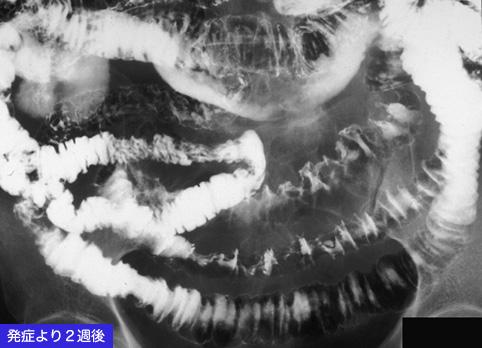

A case of an ischemic lesion due to vasculitis polymyalgia rheumatica.

Inflammatory or ulcerative disease / lesions/Ischemic colitis

Small intestine/Jejunum

X-ray

40 -